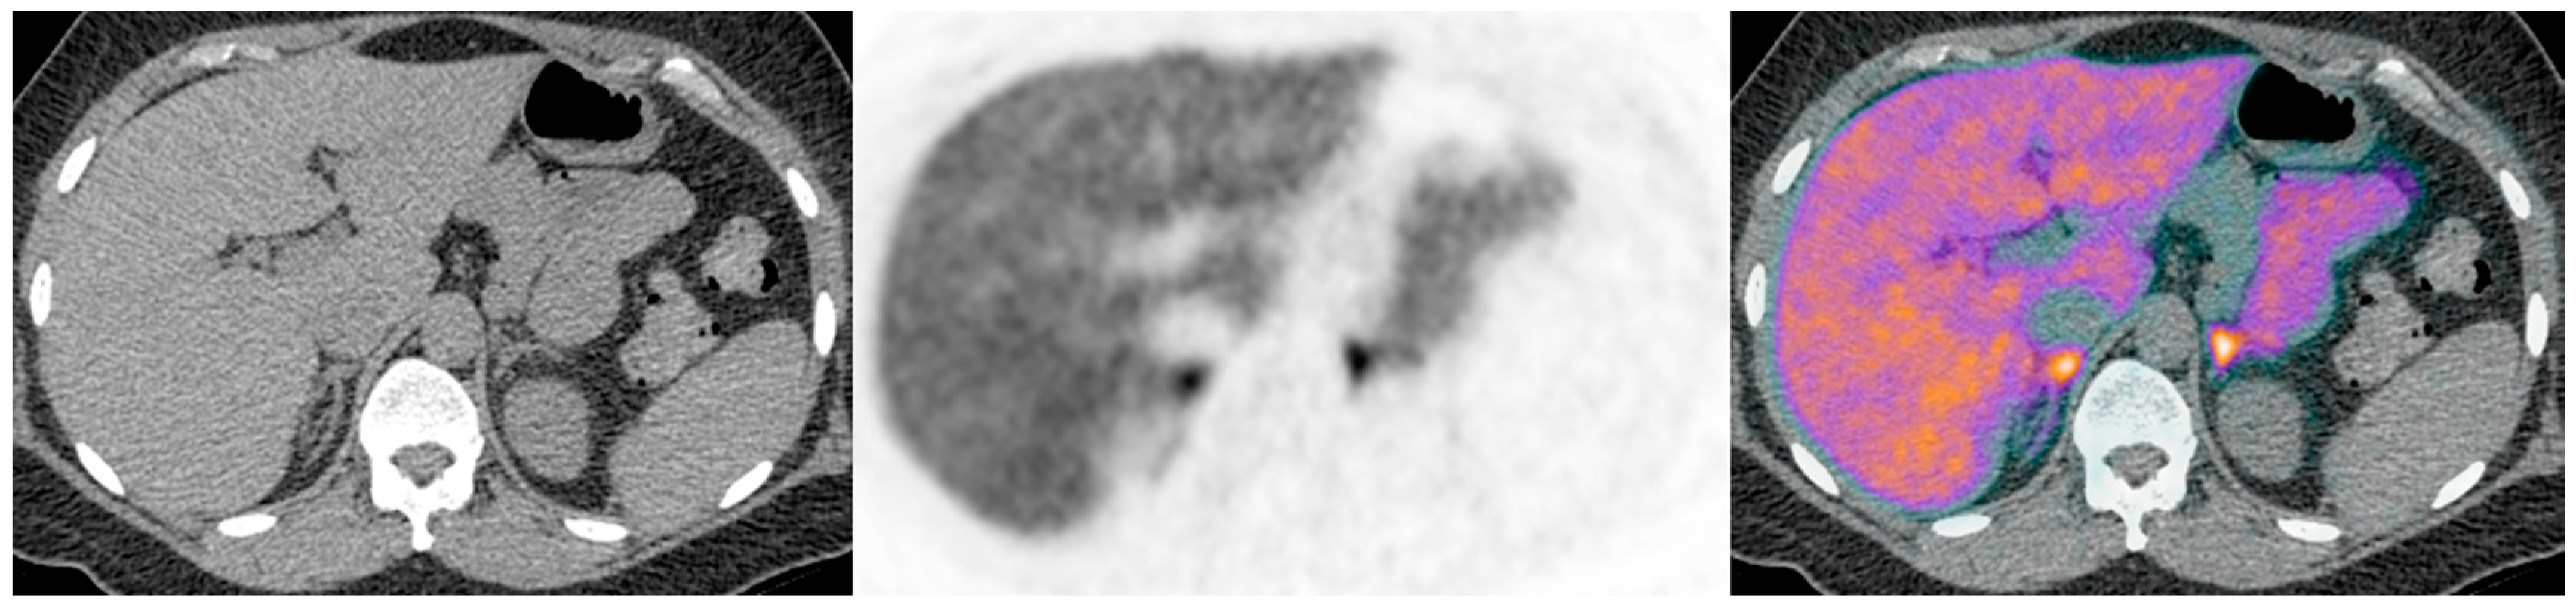

Figure 2. Illustrative case 2: A 55-year-old man with a five-year history of refractory hypertension and hypokalaemia (requiring four agents for blood pressure control) was diagnosed with primary aldosteronism (PA); CT demonstrated a 16mm left adrenal nodule (ac), which was 11C-metomidate avid, confirming unilateral PA (di). Functional imaging was performed after right adrenal vein cannulation had been unsuccessful during adrenal vein sampling. A left laparoscopic adrenalectomy confirmed a typical Conn’s adenoma. Three years post-operatively his PA remains in complete remission and he requires only a single agent (amlodipine) to achieve full blood pressure control.